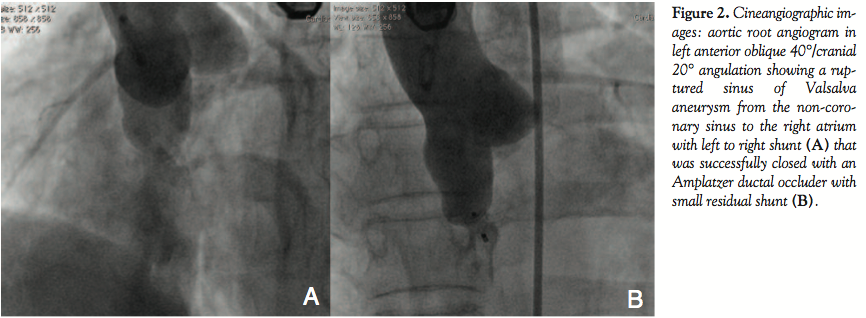

The patient was started on 150 mg aspirin/day and clopidogrel 75 mg/day. At cardiac catheterization, the aortic and pulmonary pressures were 186/58 mm Hg (mean, 100 mm Hg) and 38/12 mm Hg (mean, 20 mm Hg), respectively. The baseline left-to-right shunt was 3:1. Aortic root angiography confirmed the diagnosis (Figure 2A).

As described previously,1-3 the TCC procedure involves crossing the defect from the aortic side using a 5 Fr Judkin’s right coronary catheter and a 0.035˝ angled-tip glide wire (Terumo Inc), which is exchanged for a 300-cm long noodle wire (AGA Medical Corporation). A stable arteriovenous loop was established by snaring the noodle wire from the superior vena cava by a gooseneck snare (ev3 Endovascular Inc) and exteriorizing it from the femoral vein. Using a 6 Fr delivery sheath through the femoral vein, the 10 x 8 mm first-generation Amplatzer duct occluder (ADO; AGA Medical Corporation) was positioned across the defect. The ADO was released only after confirming on TEE as well as angiography the correct position of the ADO, not causing any significant residual shunting or any increase in aortic regurgitation. The procedure was successful (Figure 2B) and there were no conduction disturbances noticed. The patient was discharged on day 4 with an uneventful course, except for PR prolongation on predischarge ECG (PR interval of 240 ms at heart rate of 60/min) (Figure 3).